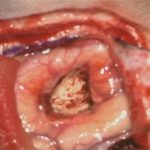

頭蓋咽頭腫

頭蓋内腫瘍摘出術

No.’25_96 手術前1

No.’25_96 手術前2

No.’25_96 摘出 前

No.’25_96  摘出 中

No.’25_96 摘出 後